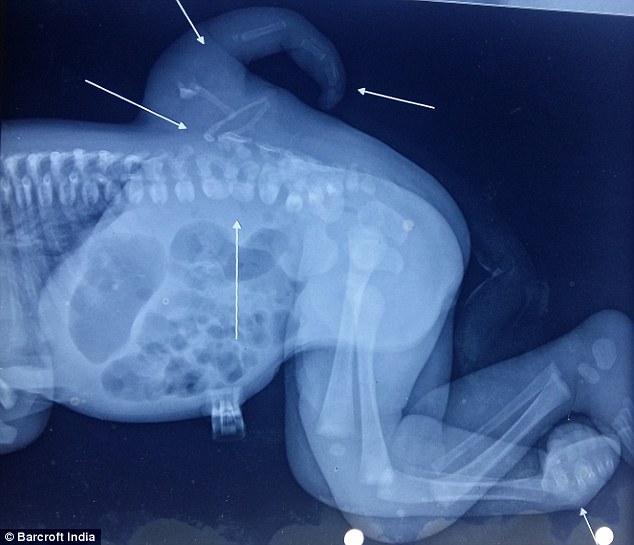

No entanto, ela foi diagnosticada com Polimelia, uma condição que fez com que uma terceira perna nascesse em suas costas, próxima à medula espinhal. Hoje com quatro anos de idade, a menina foi submetida a uma complicada cirurgia, realizada com sucesso no mês passado, para a remoção do membro extra.

A Polimelia é uma condição que afeta uma em um milhão de crianças em todo o mundo e faz com que membros extras se desenvolvam durante a formação do feto. O distúrbio ocorre quando há mutação e anomalia celular durante o desenvolvimento do feto. Às vezes, em gravidez de gêmeos, quando um dos fetos não se desenvolve completamente, alguns membros do gêmeo não desenvolvido acabam ficando atados ao corpo do outro.

De acordo com o cirurgião Dr. Daljit Singh, um dos responsáveis pela cirurgia de Varsha, um caso de Polimelia não tinha sido visto pelo corpo médico do Hospital Govind Ballabh Pant nos últimos 50 anos. “Esse foi o primeiro caso de polimelia em que a medula espinhal tinha se desenvolvido em uma perna adicional”, disse ele.